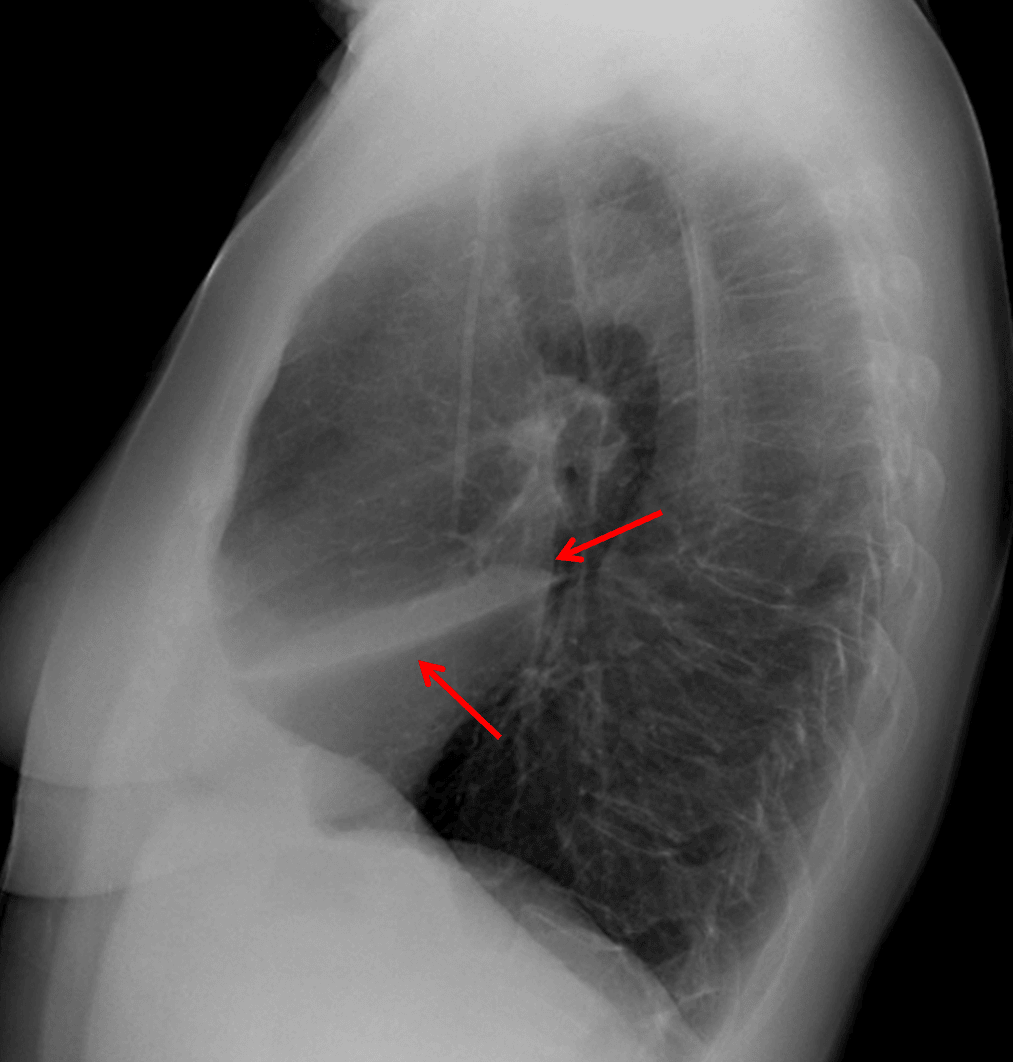

Red arrows: anterior airspace opacity sharply marginated by the major fissure inferiorly.